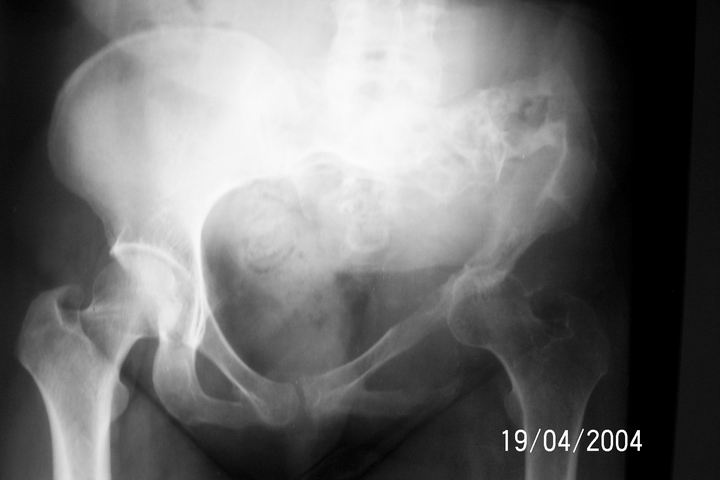

Dear All, I am attaching an x-ray of 33 - years- old female patient Biopsy report: Chondrosarcoma.

I would appreciate your inputs regarding this case.Regards